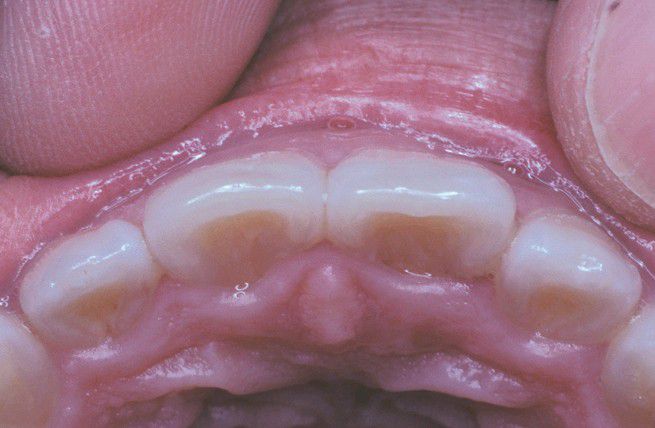

Shovel-Shaped Incisors.

Chinese patient exhibiting maxillary incisors with prominent lateral margins, which create a hollowed lingual surface.